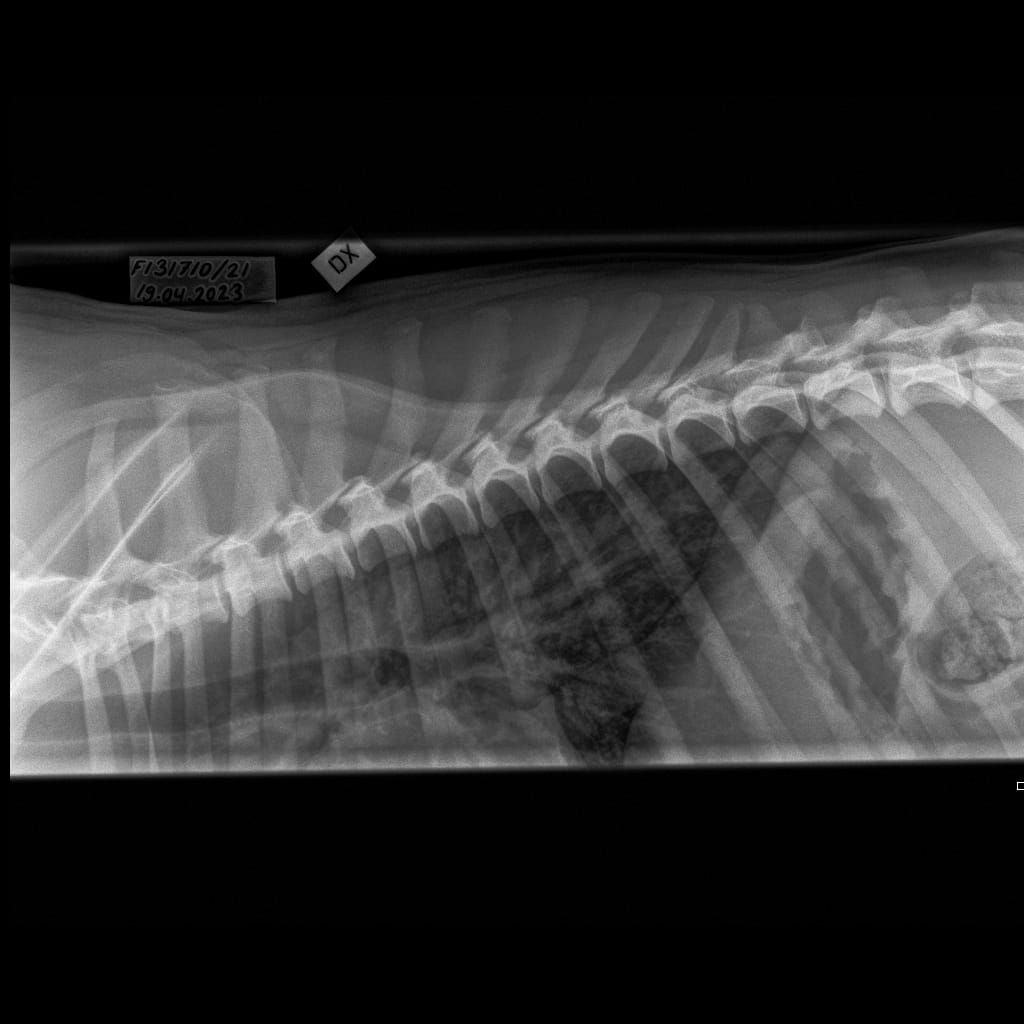

Selkäranka -Rintaranka LAT-6.11.2023-16_02_17-358 (1)